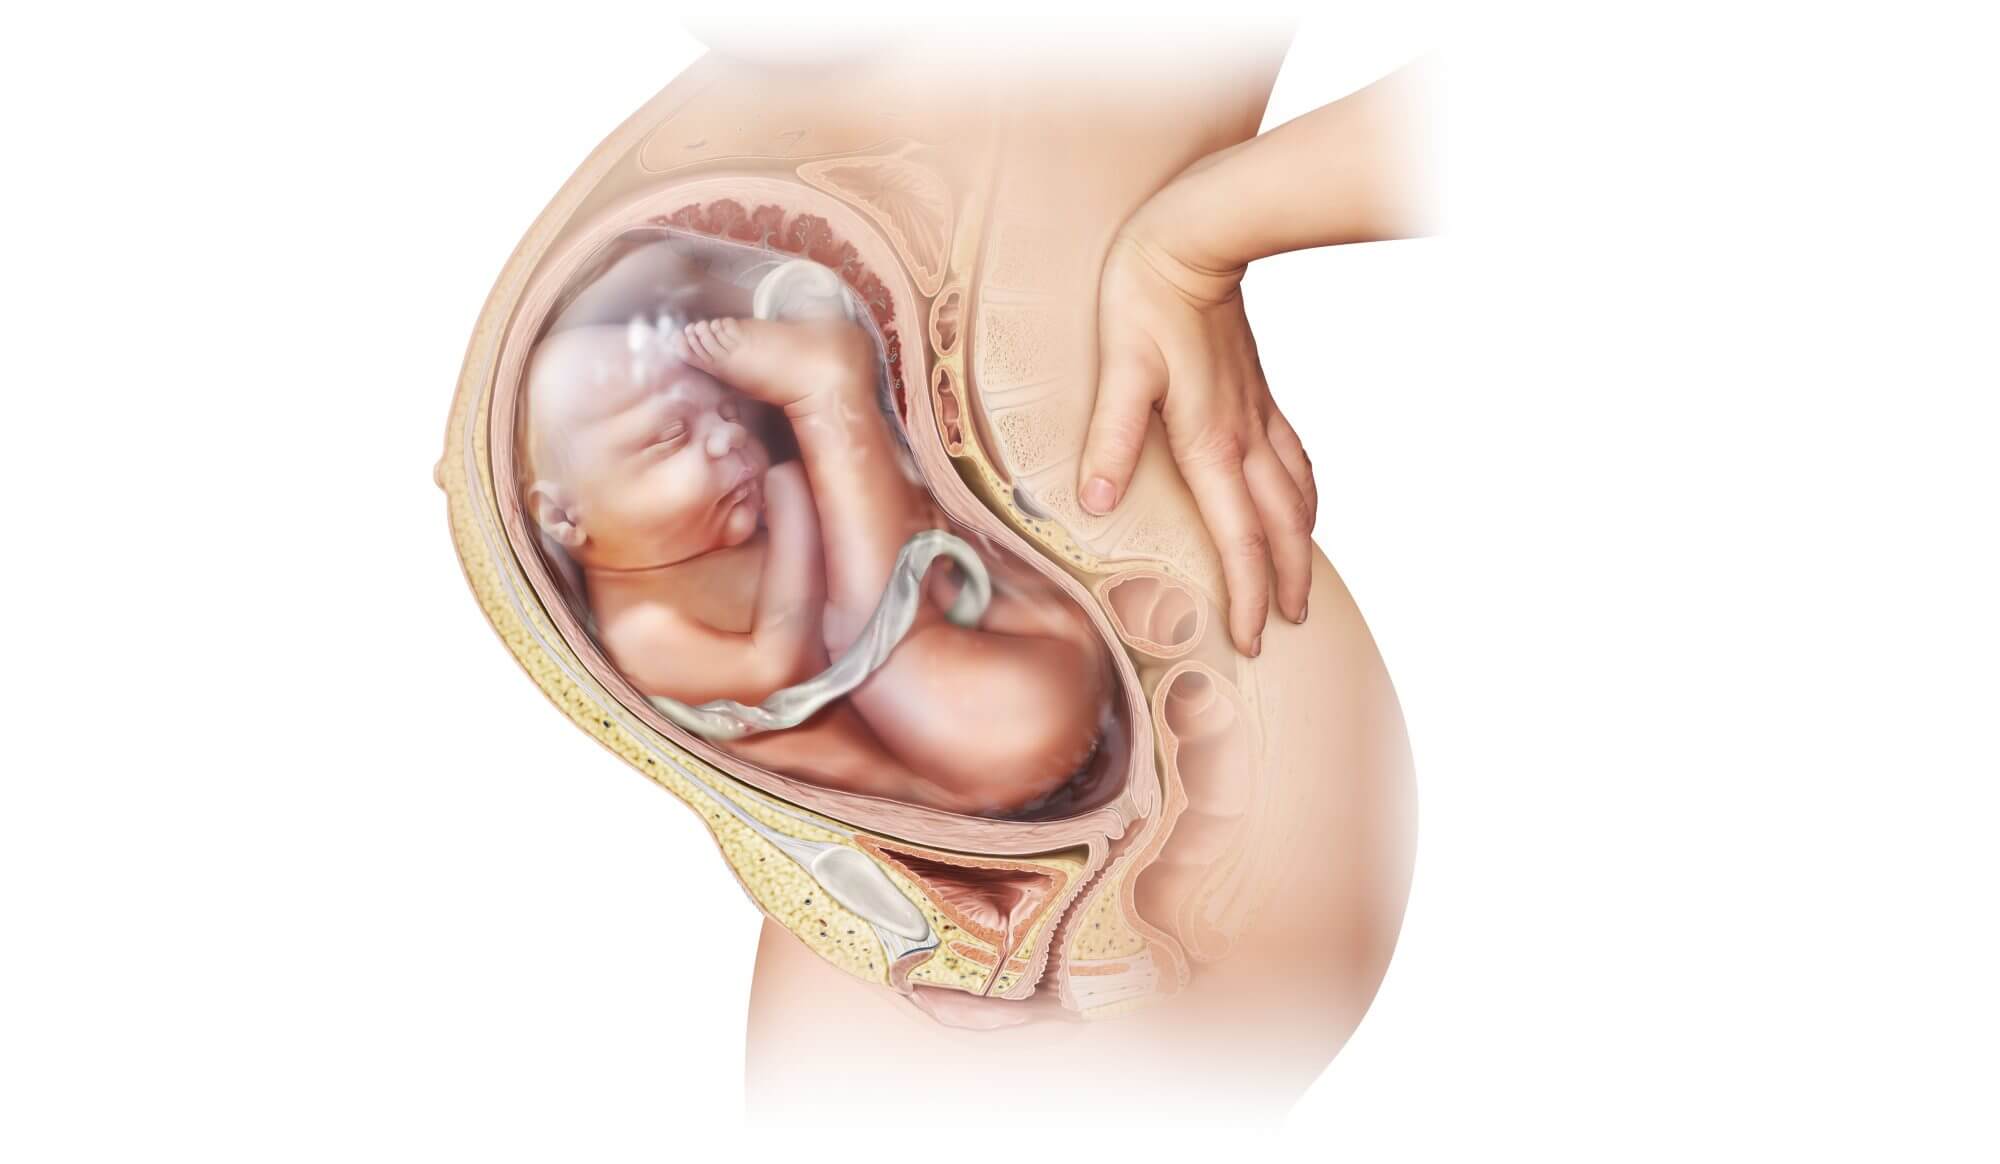

Моменты волшебства: Рождение ребенка в животе мамы

Раздел: Фотозарисовки